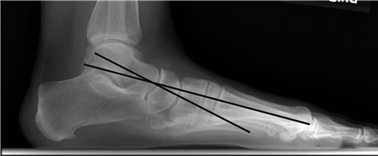

Weight-bearing anteroposterior (AP), lateral, and sesamoid axial radiographs are mandatory. On the AP view, the surgeon measures the Hallux Valgus Angle (HVA, normal < 15°), the Intermetatarsal Angle (IMA, normal < 9°), and the Distal Metatarsal Articular Angle (DMAA). The lateral view is scrutinized for Meary's angle (talo-first metatarsal angle) to identify midfoot collapse, as well as the presence of dorsal osteophytes indicative of hallux rigidus. The sesamoid axial view is critical for assessing the degree of sesamoid subluxation and the integrity of the crista.

Clinical & Radiographic Imaging Archive